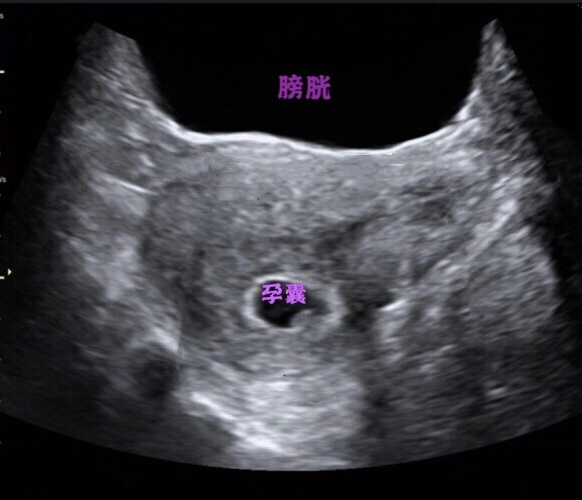

2. 早孕期

子宫、附件位于骨盆的中间,检查前憋尿,可以将肠管推开,使得子宫附件显示。这个憋尿的程度可以视女性的盆腔环境而定,如果你是一个较瘦,性卫生习惯、大便习惯良好,无盆腔手术史的人,那恭喜你,只要喝500ml水半小时后就可检查了,但相反的话,至少是1000ml半小时后才能检查,对这类的患者,更推荐是经阴道超声检查,因为经阴检查探头分辨率比腹部探头明显提高,加上探头在阴道内紧贴宫颈,所以盆腔脏器显示更清晰。